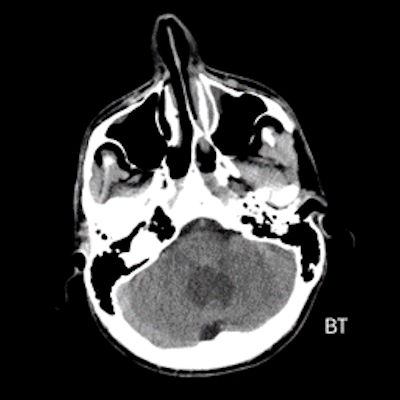

- A) Beyin BT incelemede; posterior fossada hipodens, düzgün sınırlı kistle beraber (oklar), posteriorunda 8 mm boyutunda, iyi sınırlı, kontrastsız BT’de parankim ile izodens, postkontrast görüntülerde yoğun kontrast tutulumu gösteren mural nodül komponenti (oklar) gözlenmektedir.

- BT’de tipik olarak iyi sınırlı, hipodens kistik bir lezyon ve içinde belirgin şekilde kontrastlanan mural nodül izlenir.

- Kalsifikasyon: Hemanjioblastomlarda kalsifikasyon çok nadirdir (oligodendrogliom ve ependimomlardan ayırt edici bir özellik).